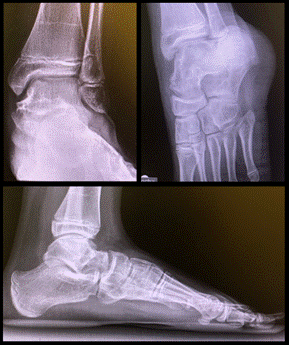

Se realizaron controles clínicos e imagenológicos a la semana y 2 semanas luego de la cirugía. Luego al mes, a los 3 y 6 meses. Por último, al año y a los 3 años posteriores a la lesión.

Destacamos la presencia del signo de Hawkins positivo en el control imagenológico a los 3 meses luego de la lesión, siendo este un elemento que nos indica preservación de la vascularización del astrágalo.

Del control a los 3 años luego de la intervención quirúrgica se destaca una excelente evolución clínica. Se realizó la escala AOFAS, con previo consentimiento de los padres, obteniendo una puntuación de 93/100. No presentó limitaciones en cuanto al dolor, con un total de 40 puntos, no mostró limitaciones en cuanto a la función, con un total de 45 puntos. Observamos una leve desaxación en valgo del retropie, asintomático, con un total de 8 puntos.